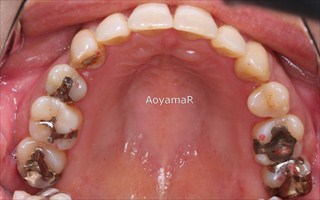

そう生(歯並びのガタガタ、乱杭歯、八重歯)の矯正症例

CASE 12

(34歳 女性 )

上顎第一小臼歯2本抜歯による叢生の除去

マウスピース型カスタムメイド矯正装置(インビザライン)単独による治療

治療前